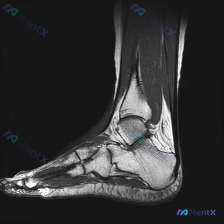

整理了一份足踝MRI读片病例,分享下分析思路,大家可以一起讨论。 病例影像基础信息 这是一张足踝部T2加权矢状位MRI,显示跟骨、距骨、部分跗骨和足底结构: - 骨骼:跟骨和距骨骨髓信号基本正常,皮质边缘清晰,未见明显异常信号 - 关节:跟距关节间隙清晰,无明显关节面侵蚀或严重狭窄 - 异常发现:跟...

最近看到一份踝关节MRI读片请求,问题是「影像中能观察到什么?提示软组织积液」,整理了完整的读片和分析思路,和大家分享讨论。 一、影像基本信息 这是踝关节矢状位MRI T2序列,影像观察结果如下: 1. 骨结构:胫骨远端、距骨、跟骨、舟骨、部分楔骨骨皮质轮廓完整,胫距关节间隙可见 2. 关节腔:胫距...

踝关节MRI读片病例分享,整理了完整分析思路 这是一例踝关节矢状位T2加权MRI,我把影像发现和分析思路整理出来,和大家一起讨论。 一、基本影像信息 这是踝关节MRI T2序列矢状位图像,可观察到胫骨远端、距骨、跟骨及周围软组织结构,核心阳性征象如下: 1. 骨骼关节改变:距骨穹窿(圆顶)可见明确局...